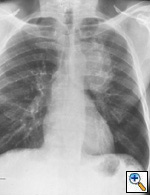

Fig. 16a: Posterior-anterior chest radiograph shows a large central bronchogenic carcinoma on the left; questionable involvement of mediastinum or vascular structures, T3 or T4.